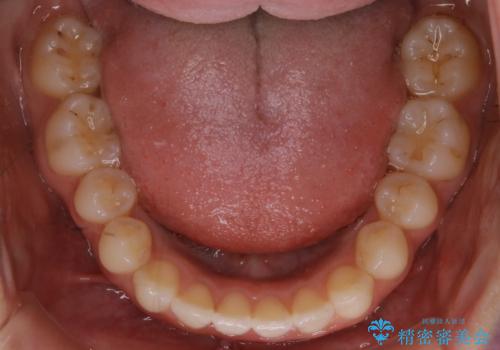

- 前から2番目の歯が捻じれていることが気になるとご相談にいらした方です。

インビザラインFULLで治療を行いました。

上の前から2番目の歯は、一般的に周囲の歯と比べて小さく、動きづらい歯であると言われています。前歯にゴムかけを行うことで理想的な位置まで歯を動かしてくることが出来ました。